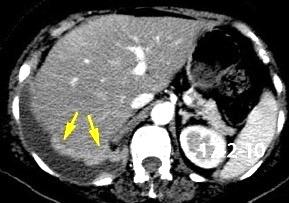

Absceso secundario a perforación de carcinoma. 3-4%. En flexura esplénica puede tener absceso subfrénico o empiema.

Empiema pleural secundario a carcinoma de la flexura esplénica (masa visible)

Lian R et al. Empyema caused by a colopleural fistula. Medicine (Baltimore) 2017/Osada T,, et al. Thoracic empyema associated with recurrent colon cancer: report of a case and review of the literature. Dis Colon Rectum 2001